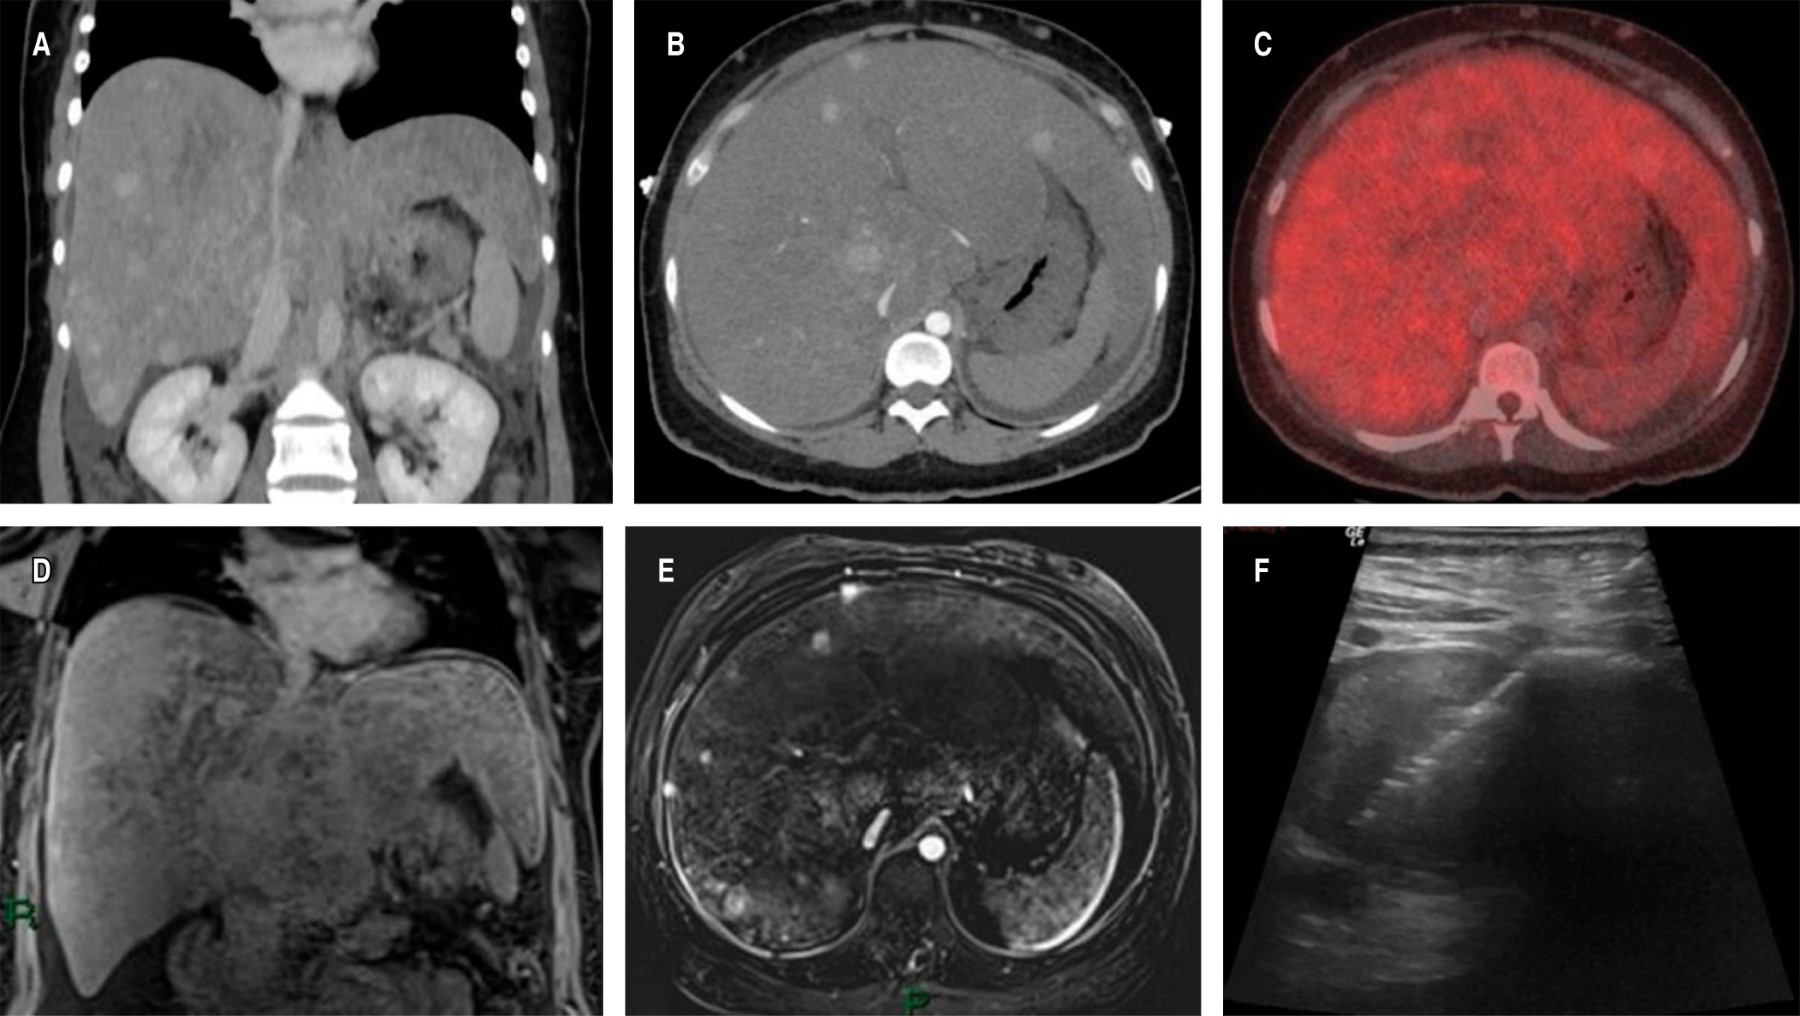

Se realizó una tomografía abdominal con contraste intravenoso (Figura 3), donde se reportó y corroboró la presencia de hepatomegalia asociada a presencia de múltiples lesiones focales de origen por determinar, la mayor se localizaba en el segmento I y con posibles cambios inflamatorios, lo cual condiciona compresión de la vena cava inferior, importante colateralidad venosa y ascitis. Se completa abordaje con una resonancia magnética abdominal contrastada, la cual confirmó la presencia de hepatomegalia con múltiples lesiones nodulares e hipervasculares (Figura 3); disminución del calibre de las venas suprahepáticas, venas portales y de la vena cava inferior, éste último con un trombo en su interior de probable etiología tumoral.

Figura 3